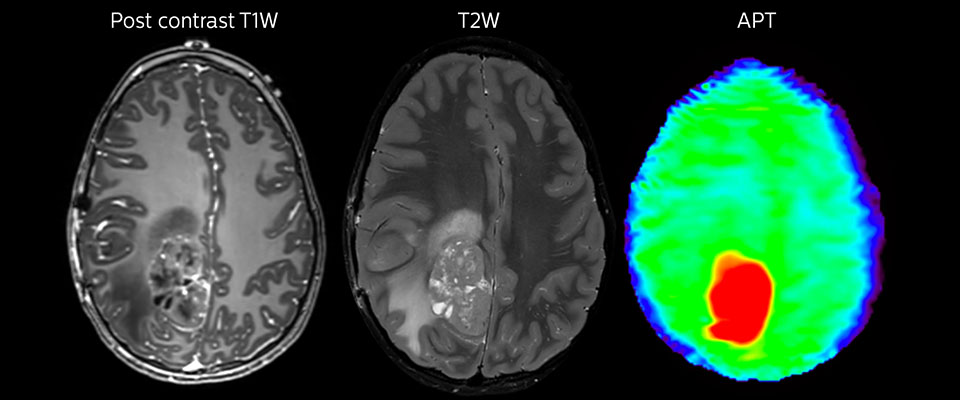

Large metastatic brain lesion

This 10-year-old patient underwent Ewing’s sarcoma tumor resection 7 years ago, but was found to now have a large metastatic lesion in the brain. This lesion shows clearly increased APT signal.

MRI with APT post resection

Immediately post resection MRI was again performed. T2-weighted and postcontrast T1-weighted images are quite inconclusive for distinguishing residual tumor tissue from postoperative tissue changes. On the APT image some high signal is still seen, which would suggest residual tumor tissue.